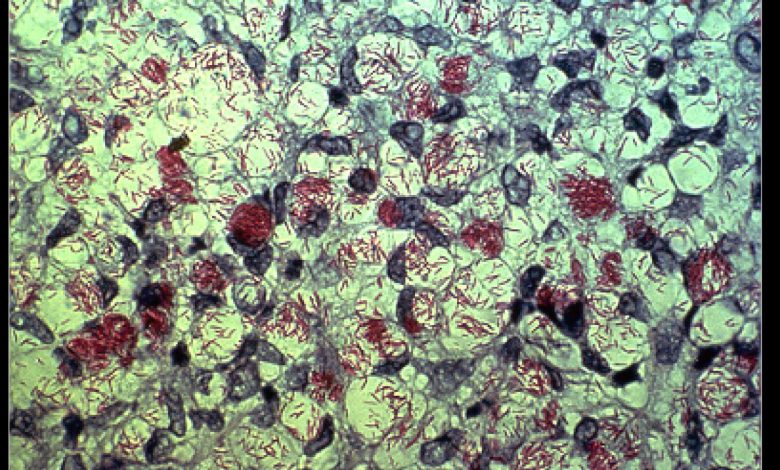

M. leprae, um dos agentes causadores da lepra. Crédito: Domínio Público

Esse longo período de incubação deu à bactéria causadora da lepra, Mycobacterium leprae, muito tempo para se espalhar por seu corpo.

Seu laboratório é um dos poucos no mundo capaz de fazer testes com a bactéria da lepra, que não sobrevive em placa de Petri.